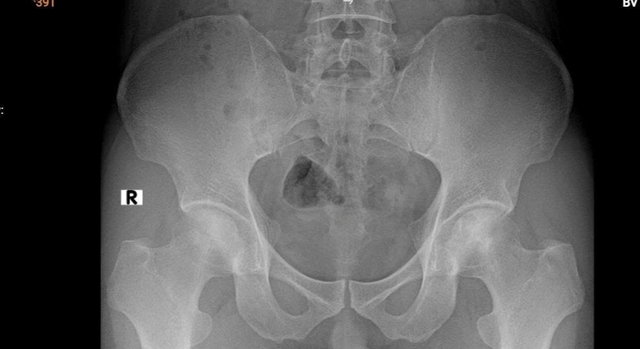

Kết quả chụp MRI cho thấy phần chỏm xương cánh tay trái bị hoại tử, ổ hoại tử lan xuống vùng cổ và thân xương cánh tay. Khi chụp X-quang phần khớp háng nhận thấy dấu hiệu hoại tử vô mạch chỏm xương đùi hai bên độ 2 theo ficat và alert (tình trạng tế bào xương ở chỏm xương đùi chết đi do mất nguồn cung cấp máu).

Bệnh nhân có dấu hiệu hoại tử vô mạch chỏm xương đùi hai bên độ 2 theo ficat và alert.